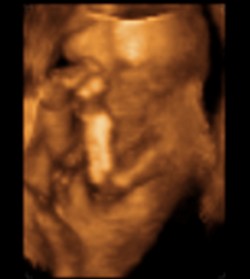

Kép A kis futyis (pito=futyi)

Rita! Gratula a kis kukishoz!!!!! Csodaszép!